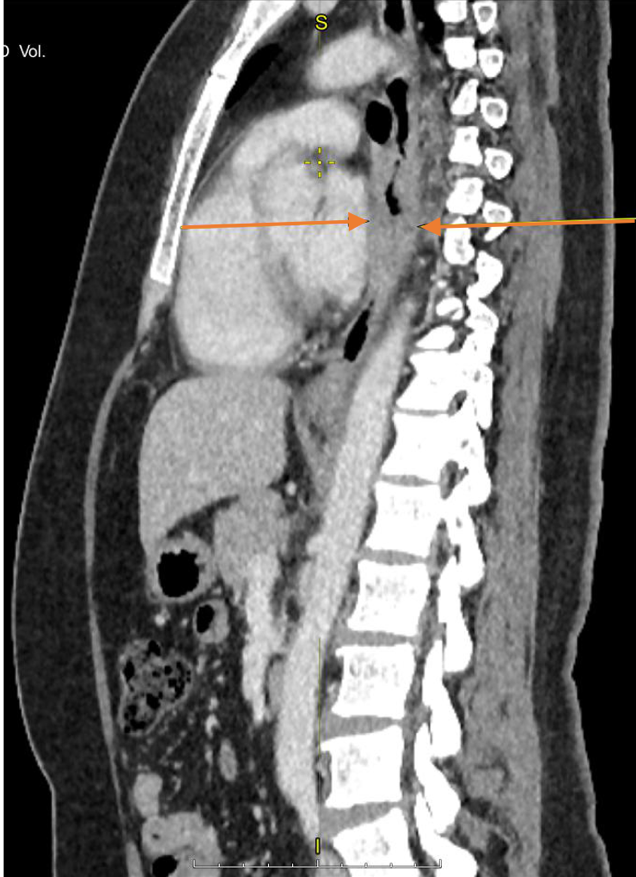

Материал и методы. Представлено 3 клинических случая одновременного развития плоскоклеточного рака пищевода и аденокарциномы желудка у пациентов, получавших лечение в ГУЗ «Областной клинический онкологический диспансер», г. Ульяновск, и ГАУЗ СО «Свердловский областной онкологический диспансер», г. Екатеринбург. Пациентам проведены хирургическое вмешательство, химиотерапия и лучевая терапия.

Результаты. Первично-множественный синхронный плоскоклеточный рак пищевода и аденокарцинома желудка представляют собой сложную клиническую задачу, требующую вмешательства мультидисциплинарной команды специалистов. Химиолучевая терапия с использованием схемы FOLFOX продемонстрировала хорошую переносимость и позволила достичь удовлетворительного клинического ответа со стороны опухолей обеих локализаций.